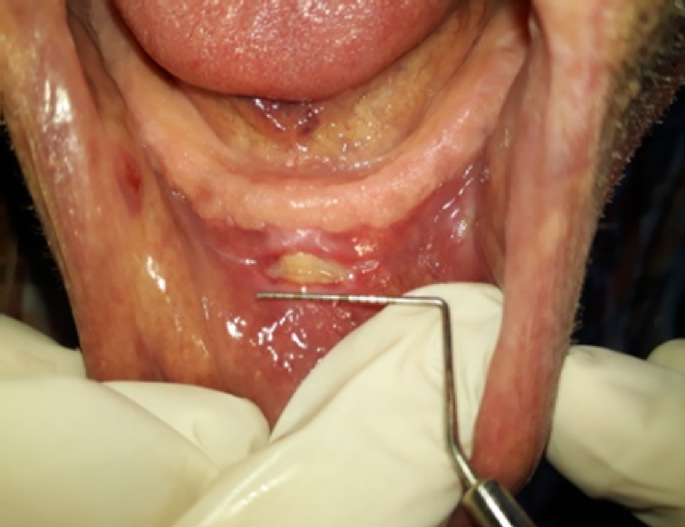

All data collection, denture adjustments, and ulcer evaluations were conducted by a single operator (the primary author) to maintain methodological consistency. At each follow-up, the location, number, and size of ulcers were documented using a structured, self-designed form. Pressure-indicating paste (Dentaseem) was applied to the intaglio and border surfaces of the dentures to identify pressure spots1. Traumatic ulcers were marked using a copying pencil, and adjustments were performed using tungsten carbide burs followed by smoothing with fine-grit sandpaper. Patients were advised to remove their dentures on the day of the adjustment and the following day to facilitate mucosal healing (Figs. 1 and 2).

(A) Traumatic ulcer at first visit (before adjustment). Figure 1 (B) Traumatic ulcer at second visit (after adjustment).